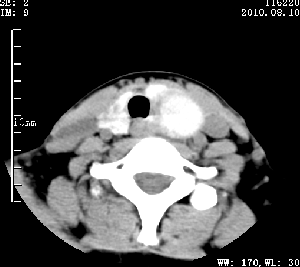

标题: CT28317:病人近几天无意间发现颈部肿块。 [打印本页]

标题: CT28317:病人近几天无意间发现颈部肿块。

甲状腺左叶局限性结节性甲状腺肿可能。建议增强扫描。

病变边界清楚,周围间隙清晰,甲状腺左叶(甲状旁腺?)肿大,右叶甲状腺腺瘤。

病变边界清楚,周围间隙清晰,左叶甲状腺肿大,右叶甲状腺小腺瘤。